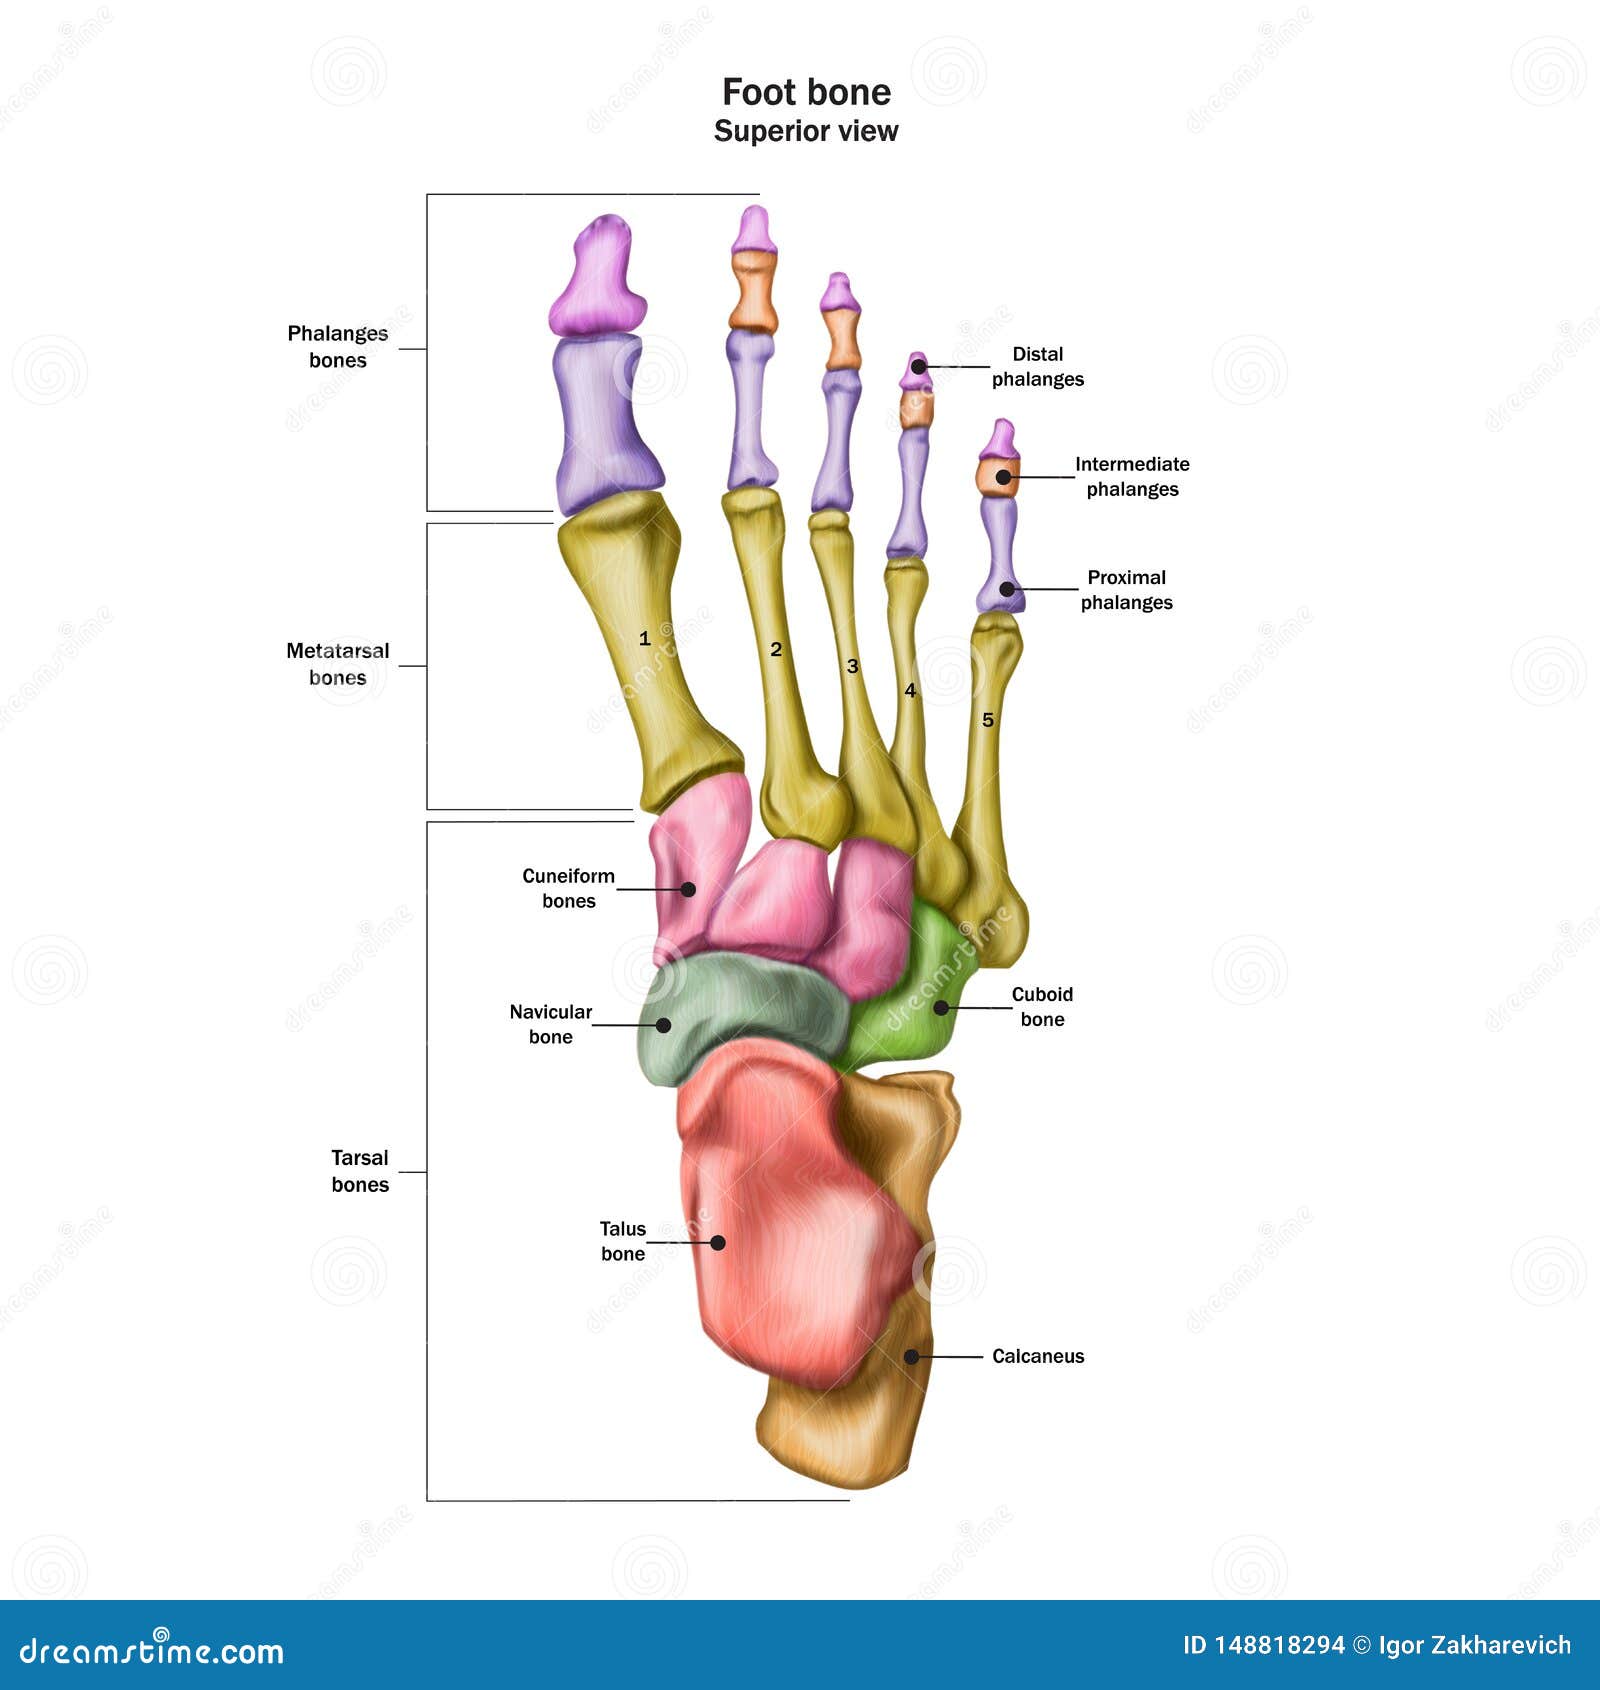

Anatomia Delle Ossa Dei Piedi Illustrazione Di Stock - Illustrazione Di

it.dreamstime.comFoot Bones With Explanation. Stock Vector - Image: 65669090

it.dreamstime.comFoot Bones With Explanation. Stock Vector - Image: 65669090

dreamstime.compiede ossa anatomie verklaring spiegazione explication explanation segno

dreamstime.compiede ossa anatomie verklaring spiegazione explication explanation segno

Anatomia Delle Ossa Dei Piedi Illustrazione Vettoriale - Illustrazione

Bones Of The Foot And Ankle Joint Medical Vector Illustration Isolated

de.dreamstime.compiede ossa cheville articolazione caviglia pied fuß articulation knochen isolated infographic osso

de.dreamstime.compiede ossa cheville articolazione caviglia pied fuß articulation knochen isolated infographic osso

Bones Of The Foot, Labeled Royalty Free Stock Photo - Image: 8616465

www.dreamstime.compiede ossa knochen foot beschriftet fusses contrassegnate calcaneus phalanges fersenbein tarsals fußes anatomy

www.dreamstime.compiede ossa knochen foot beschriftet fusses contrassegnate calcaneus phalanges fersenbein tarsals fußes anatomy

www.sanitariabresciana.comAnatomia Delle Ossa Del Piede Umano Con Descrizioni. Diagramma

www.sanitariabresciana.comAnatomia Delle Ossa Del Piede Umano Con Descrizioni. Diagramma